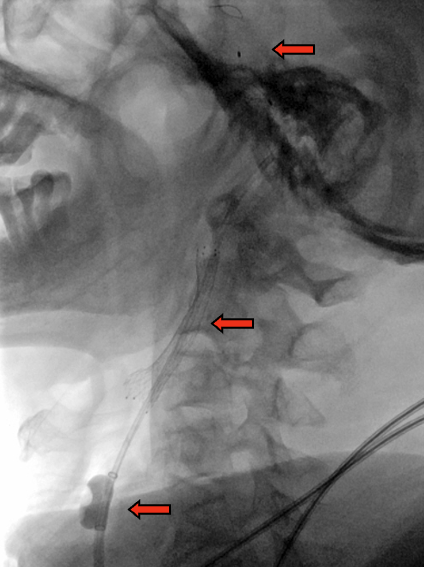

路图引导下,BGC置于颈总动脉,病变近端充盈球囊

球囊充盈后,手推造影,造影剂滞留能进一步明确狭窄病变特征。开放阀门(stopcock),可见造影剂回流,提示反向血流建立

图1. 当BGC工作时,颈总动脉、颈内动脉、颈外动脉、Willis环中颈内动脉的血流方向示意图。(注:箭头代表血流方向)